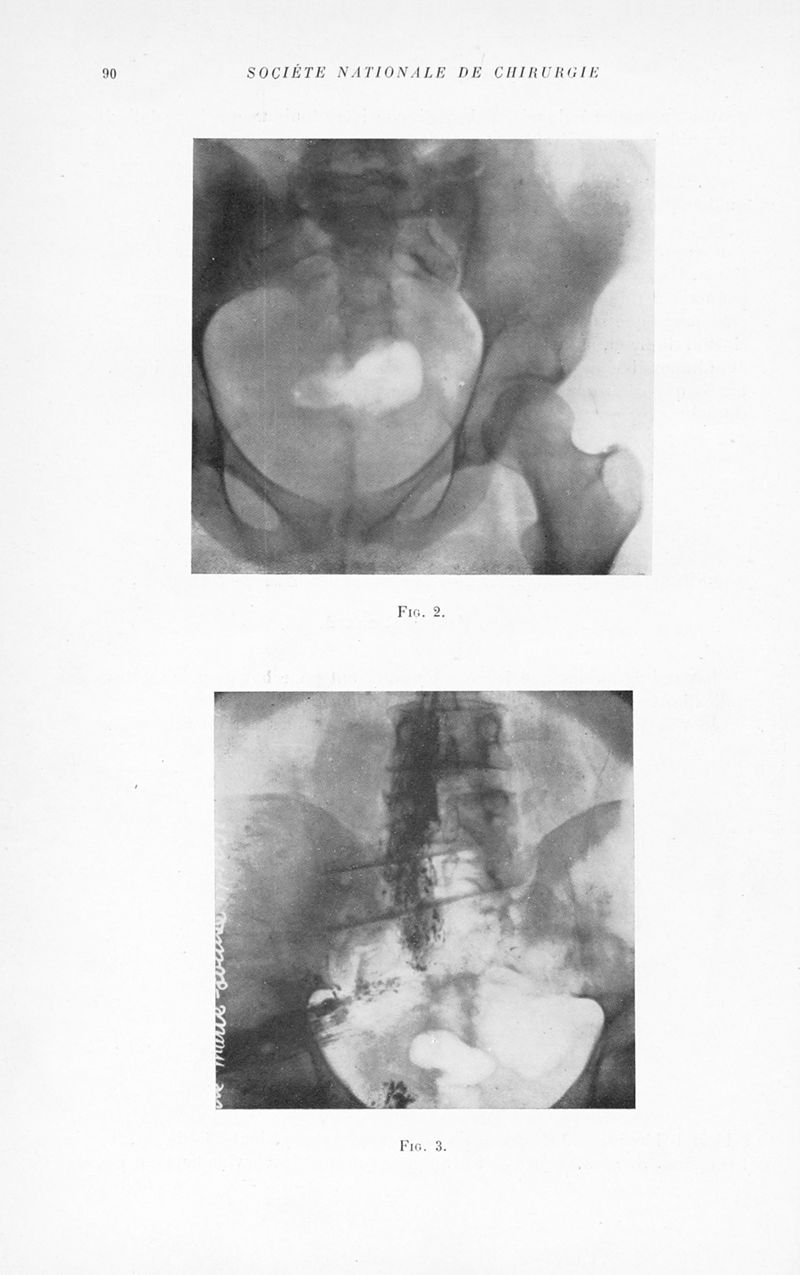

Bulletins et mémoires de la société nationale de chirurgie

Tome LIX, 1933. - Paris : Masson, 1933.